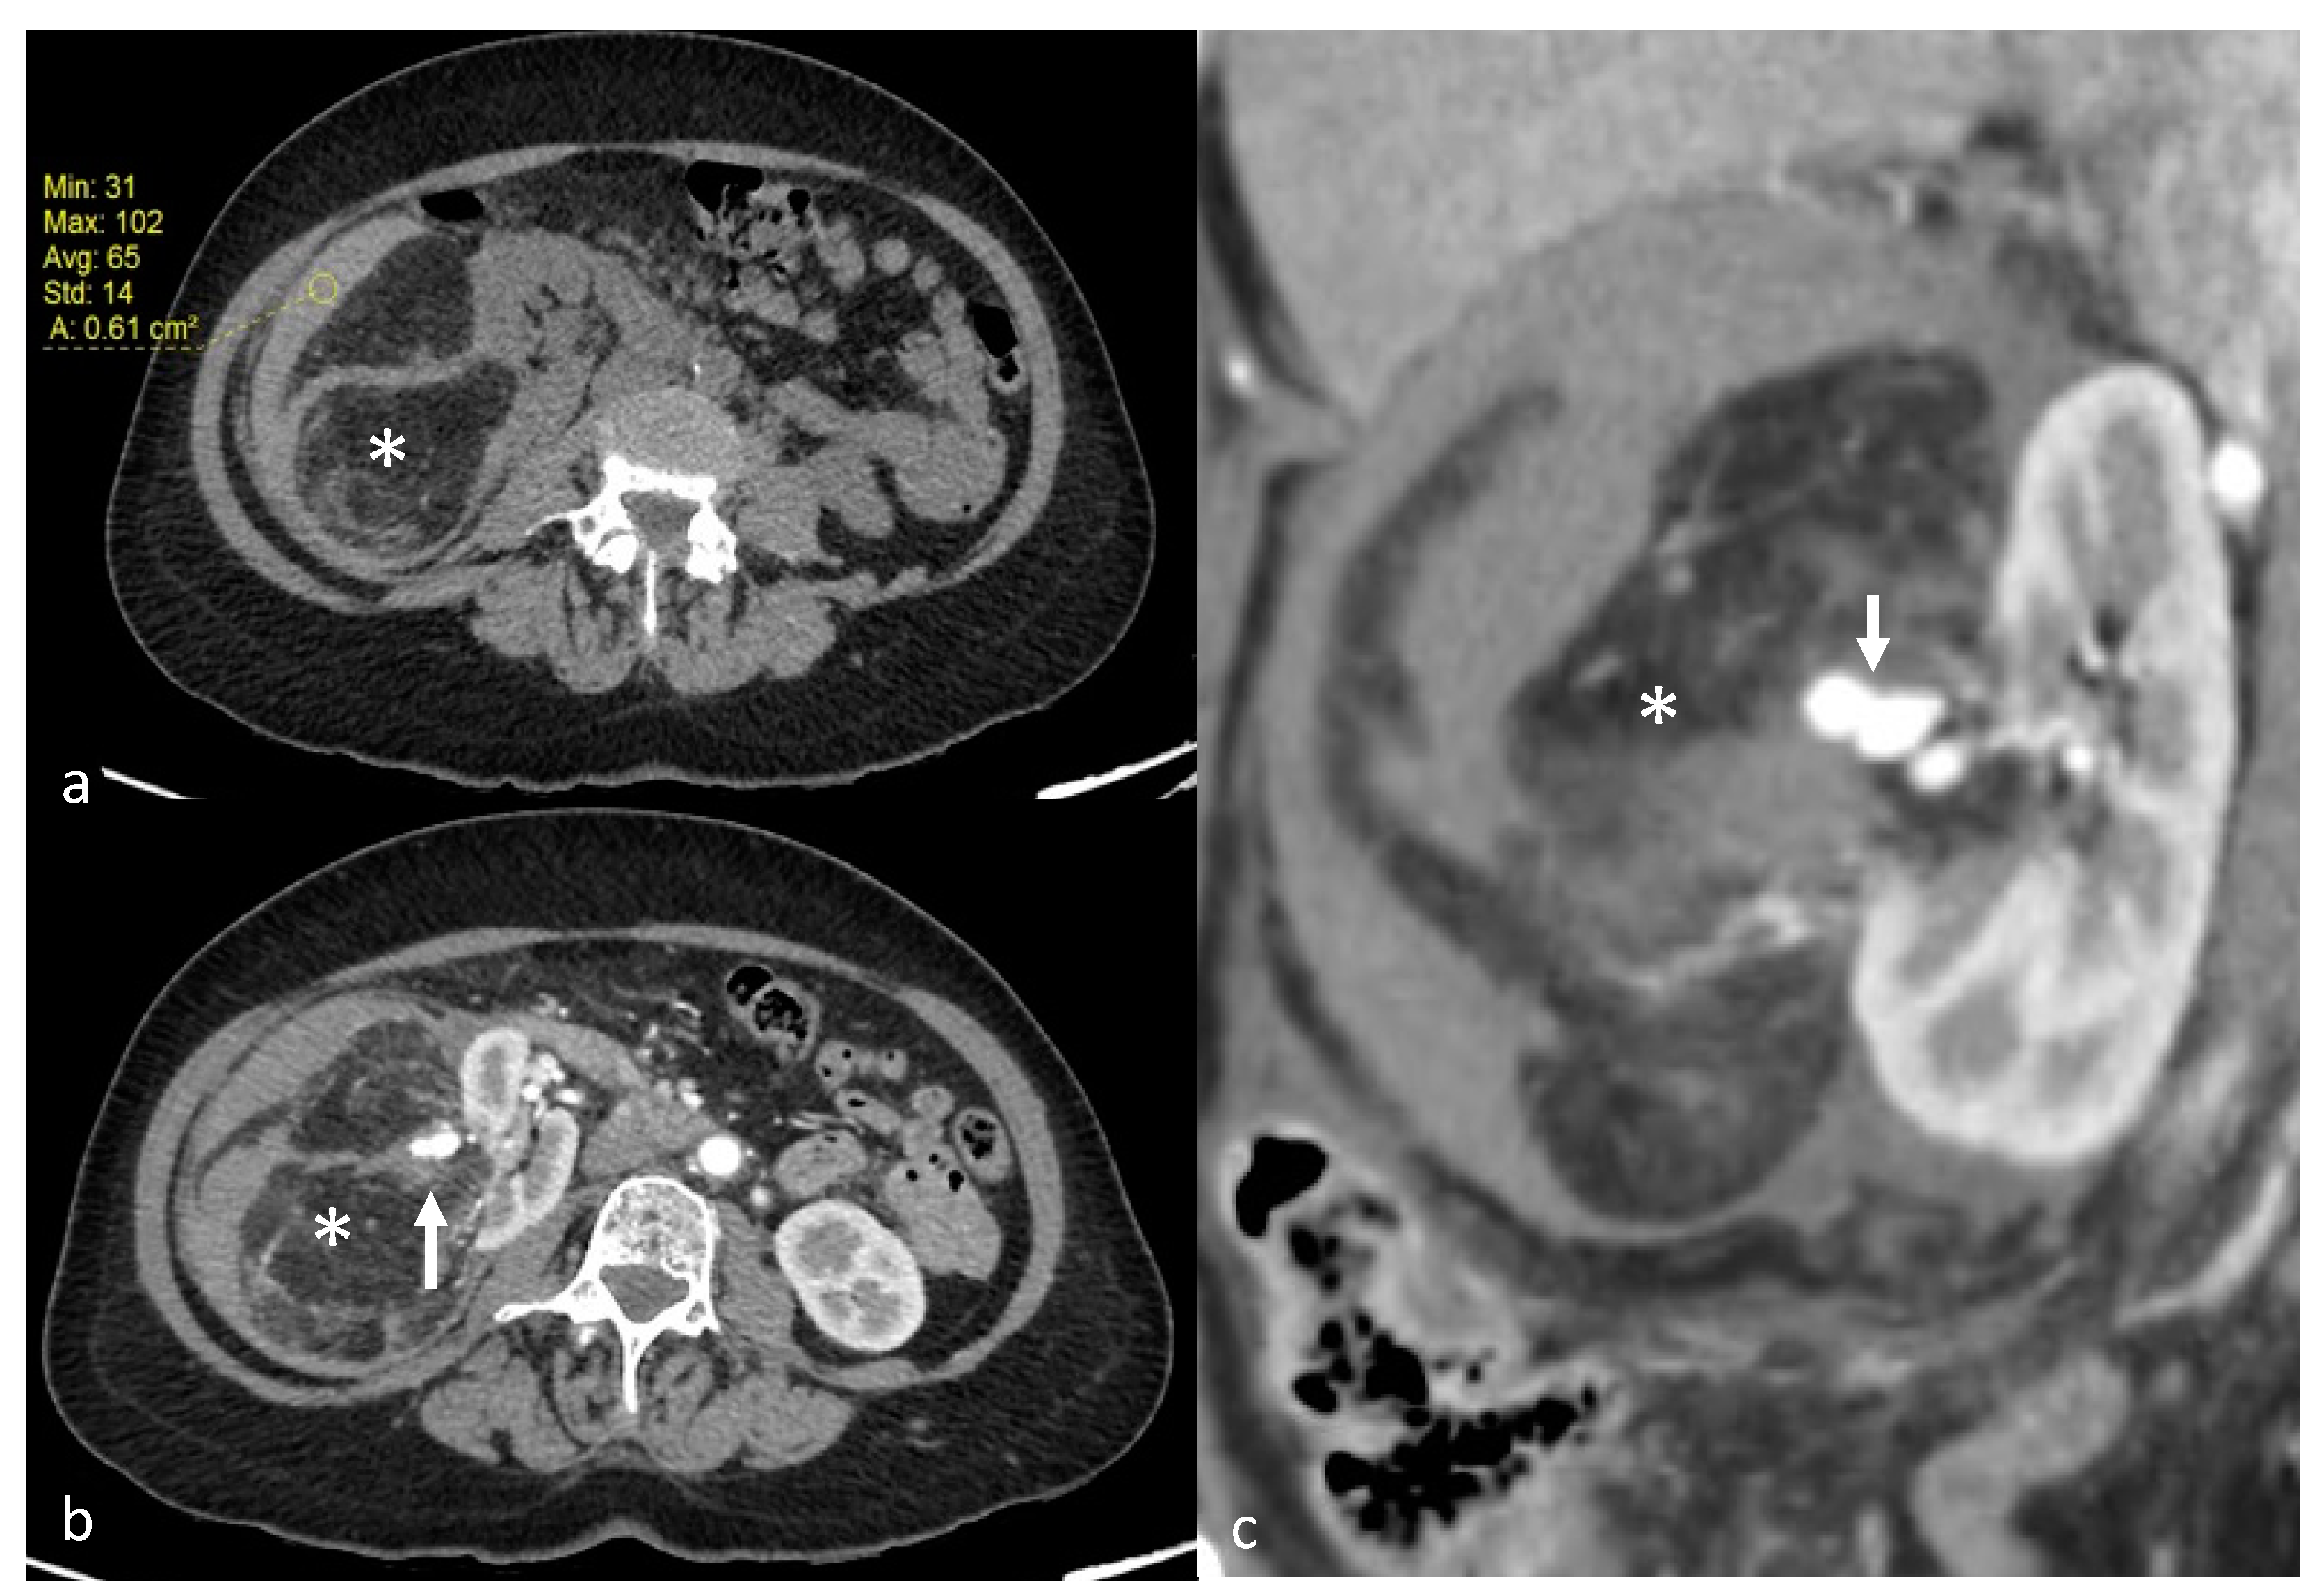

Figure 1.

A 70-year-old patient with right AML (*), Wunderlich Syndrome and aneurysm (white arrow). (a) Yellow ROI showing retroperitoneal hemorrhage (65 UH) on axial computed tomography without injection; (b) Axial computed tomography with injection and arterial acquisition; (c) Coronal computed tomography with injection and arterial acquisition.

AML were diagnosed on the basis of macroscopic fat content and the absence of calcification or necrosis at computed tomography (CT; <−20 Hounsfield Units, HU) or magnetic resonance imaging (MRI; cancellation of a high-intensity signal on T1-weighted MR images with fat saturation) [6], before treatment (Figure 1). In the absence of macroscopic fat, the use of in-phase/opposed-phase sequences, low T2W and/or ADC signal, and avid early enhancement with wash-out kinetics with or without intratumoral microscopic fat on chemical shift imaging was used for diagnosis of renal AML without visible fat [21]. In doubtful cases, a biopsy was performed (1 case). To determine the volume of AML, we used three orthogonal diameters (d1, d2, d3) measurements recorded on radiologic investigation (CT or MRI) before embolization and on the most recent CT or MRI obtained during follow-up after embolization. The AML volume was considered ellipsoid, and we used the formula as follows: (d1 × d2 × d3 × π/6) [22]. Aneurysms were diagnosed and measured on diagnostic imaging studies performed with injected contrast material (Figure 1). Patients were referred to an interventional radiologist for embolization after clinical evaluation by a urologist. Indications for TAE were an AML size threshold of greater than 40 mm maximal diameter, an aneurysm of 5 mm or greater or acute hemorrhage from an AML of any size.